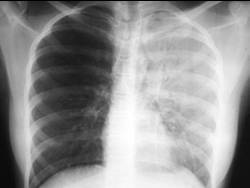

Atelectasis

Pneumonia

Effusion